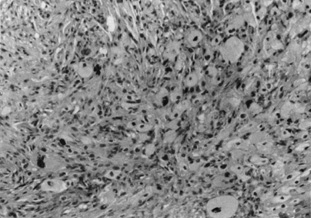

Xanthogranulomas are often a manifestation of an underlying systemic condition. Erdheim-Chester disease presents with xanthelasma, and xanthogranulomas (Fig. 13). Juvenile xanthogranuloma may be single or multiple, orange-hued, firm papulonodules on the face. They may be present at birth, but most often arise in infancy. There is a dense diffuse dermal inflammatory infiltrate characterized by large Touton multinucleated giant cells with an amphophilic center surrounded by a ring of nuclei surrounded by an external ring of foamy cytoplasm. Most lesions involute spontaneously. Xanthogranulomas may appear on the iris and produce hemorrhage and glaucoma.

Fig. 13. Erdheim–Chester Disease—This xanthogranulomatous disease is characterized by dermal infiltrate of fibrohistiocytes and Touton giant cells. The histiocytic cells are S-100 negative. (Photos courtesy of William Morris, M.D.)

Histologically, early lesions show a dense collection of histiocytes, some of which have pale, vacuolated cytoplasm. There also is an inflammatory infiltrate of lymphocytes and eosinophils. Mature lesions show the characteristic foam cells and Touton giant cells. Touton giant cells have a central wreath of nuclei surrounded by foamy cytoplasm (Fig. 14). In late lesions, the infiltrate is replaced by fibrosis.

Fig. 14. Xanthogranuloma—This Touton giant cell is characterized by a homogeneous eosinophilic center surrounded by a circle of multiple nuclei that is, in turn, surrounded by a large foamy ring (hematoxylin and eosin stain). (Photos courtesy of William Morris, M.D.)